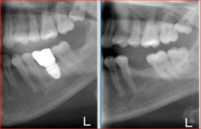

This patient’s existing old partial denture became loose after one of her teeth had broken. After thorough dental examination Dr. Andrews recommended to extract remaining lower teeth and immediately place two regular size dental implants in order to stabilize a new full lower denture.

During only one surgery three lower teeth were removed, two dental implants were placed. Three months later two snap-on attachments were placed on the integrated implants.

Her speech and chewing ability has instantly significantly improved. The satisfied patient regained quality of life she desired and expressed desire to replace the old upper denture with a new one as well.